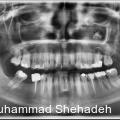

Eine 40-jährige Patientin wurde von ihrem HNO-Arzt in unsere Praxis für Mund-, Kiefer- und Gesichtschirurgie überwiesen. Die Überweisung erfolgte aufgrund eines in der Computertomografie (CT) nachgewiesenen, röntgendichten Fremdkörpers in der linken Kieferhöhle. Die Läsion wies eine Größe von etwa 7 mm auf. Klinisch klagte die Patientin über ein anhaltendes Druckgefühl im linken Mittelgesicht sowie über wiederkehrende, als „Erkältung“ wahrgenommene Beschwerden, entsprechend einer chronischen Sinusitis mit rezidivierenden akuten Schüben.